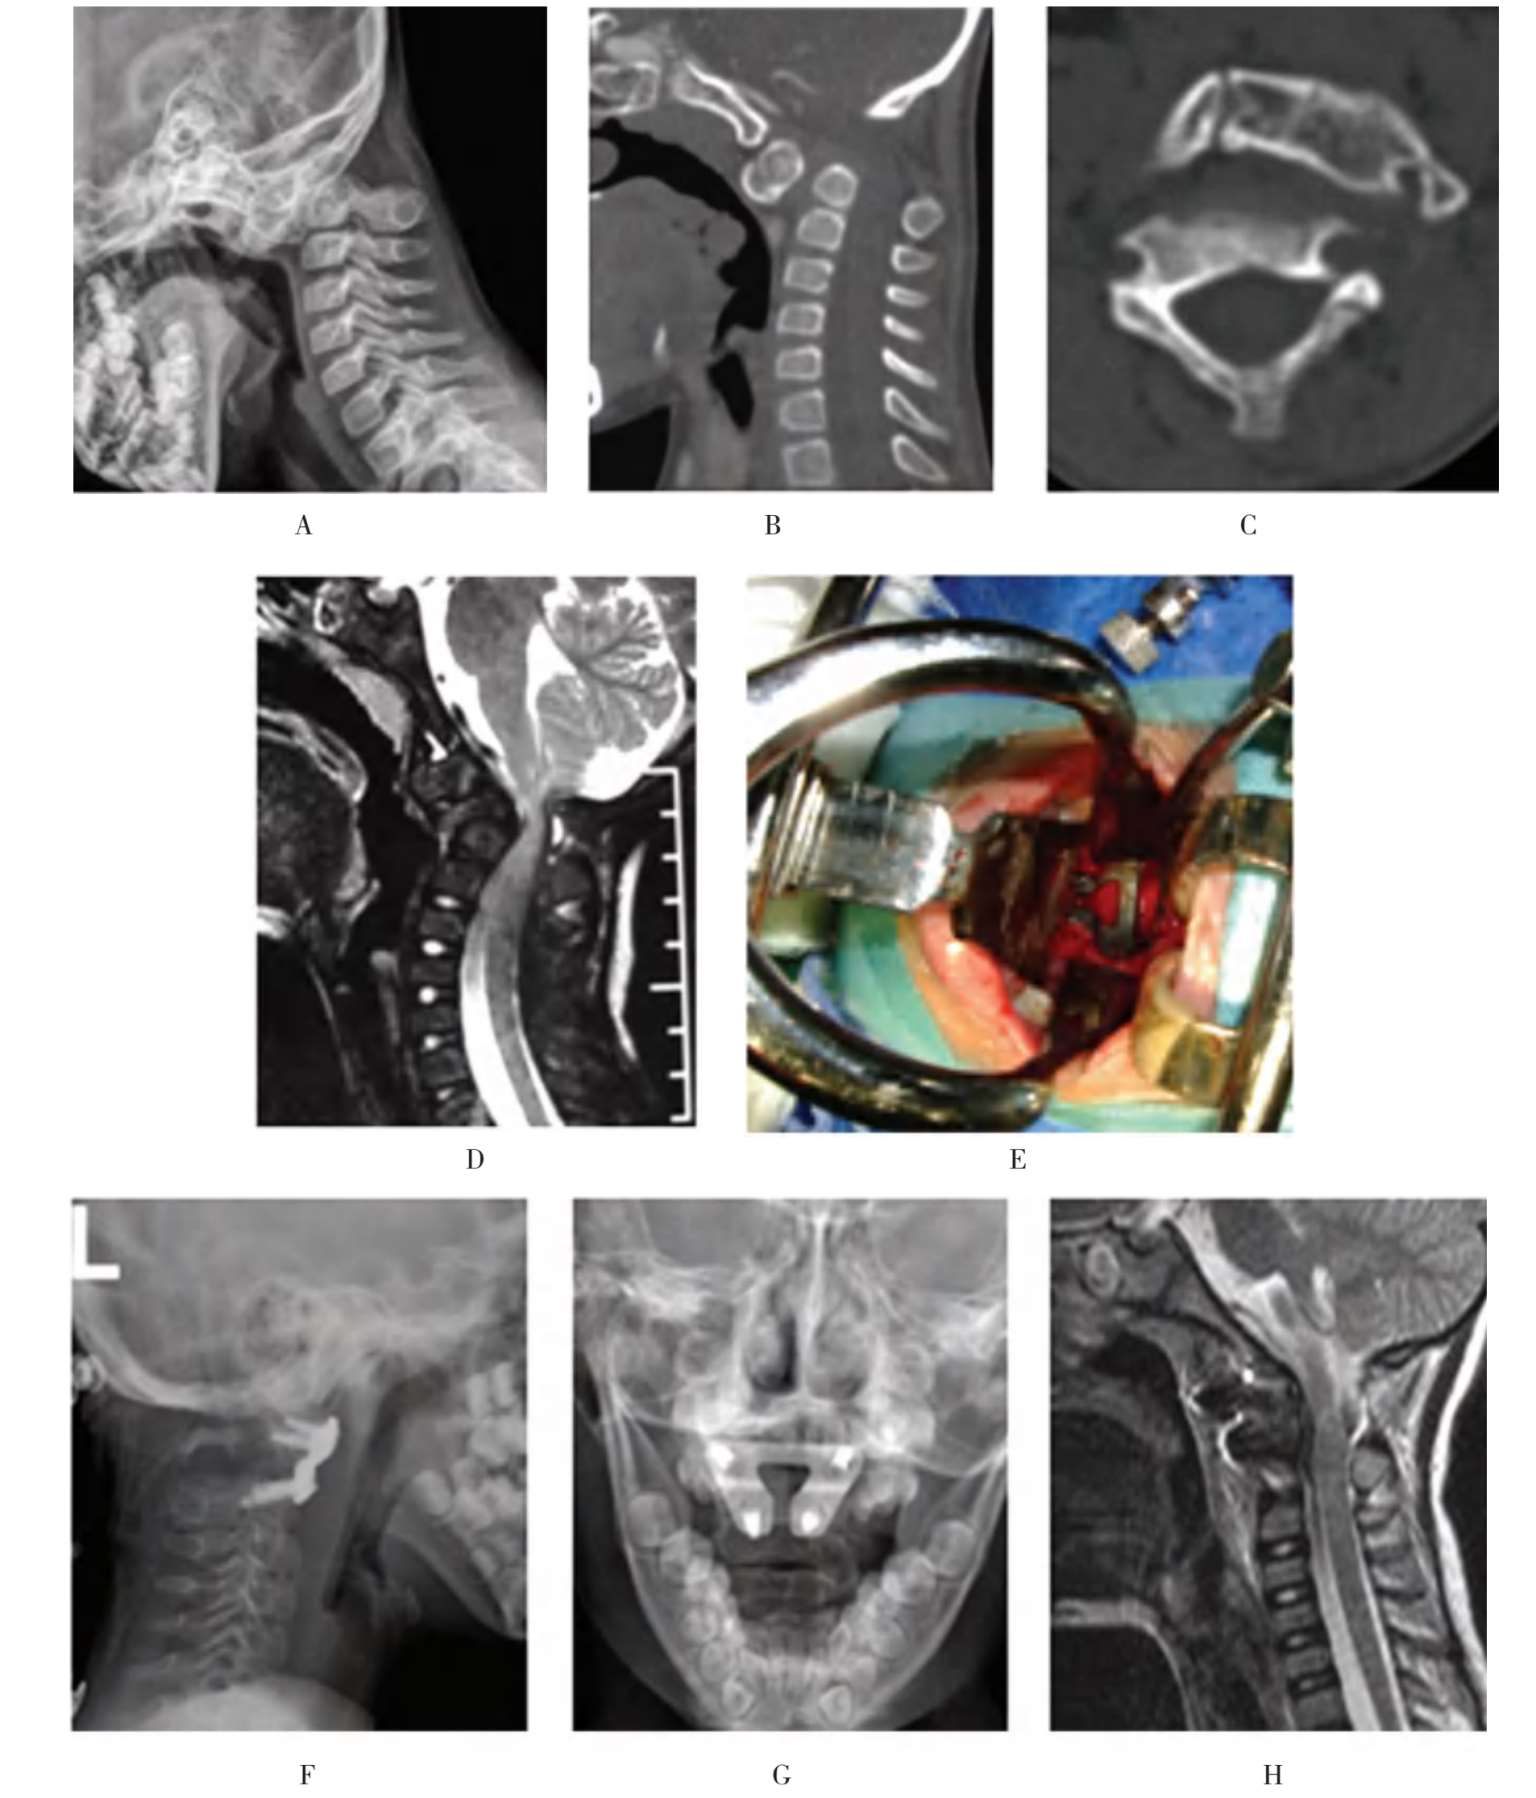

患儿,女,6岁11个月,不明原因颈痛、头颈歪斜,活动受限,伴一侧上肢疼痛麻木,走路不稳1年,加重3个月收治入院(图1-32A至图1-32C)。

患儿的颈椎CT检查提示:枢椎游离齿状突,寰椎后弓发育不良,寰枢椎脱位。

颈椎MRI检查提示:寰枢椎脱位,高位颈脊髓明显受压,变细。诊断:枢椎游离齿状突伴寰枢椎脱位。以4kg重量颅骨牵引3天后,寰枢椎复位不理想。立即行口腔准备,1周后,按计划安排经口咽前路手术治疗(图1-32D至图1-32H)。

患儿,女,6岁11个月,不明原因颈痛,活动受限,伴一侧上肢疼痛麻木,走路不稳1年收治入院。A~C.术前X线片及CT显示游离齿突伴寰枢椎脱位;D.术前三维CT显示寰椎后弓发育不良;E.在数字模型的辅助下,对患儿实施了经口咽前路复位内固定手术;F、G.术后复查的X线片显示寰枢椎脱位复位、钢板位置良好;H.术后MRI显示脊髓压迫解除

图1-32 典型病例